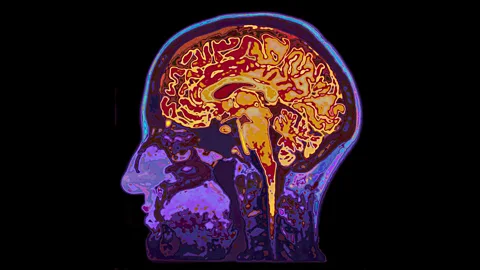

We feel that we are in control when our brains figure out puzzles or read words, says Tom Stafford, but a new experiment shows just how much work is going on underneath the surface of our conscious minds.

These are strong claims, and the authors acknowledge that there is much work to do as we start to explore the power and reach of our unconscious minds. Like icebergs, most of the operation of our minds remains out of sight. Experiments like this give a glimpse below the surface.